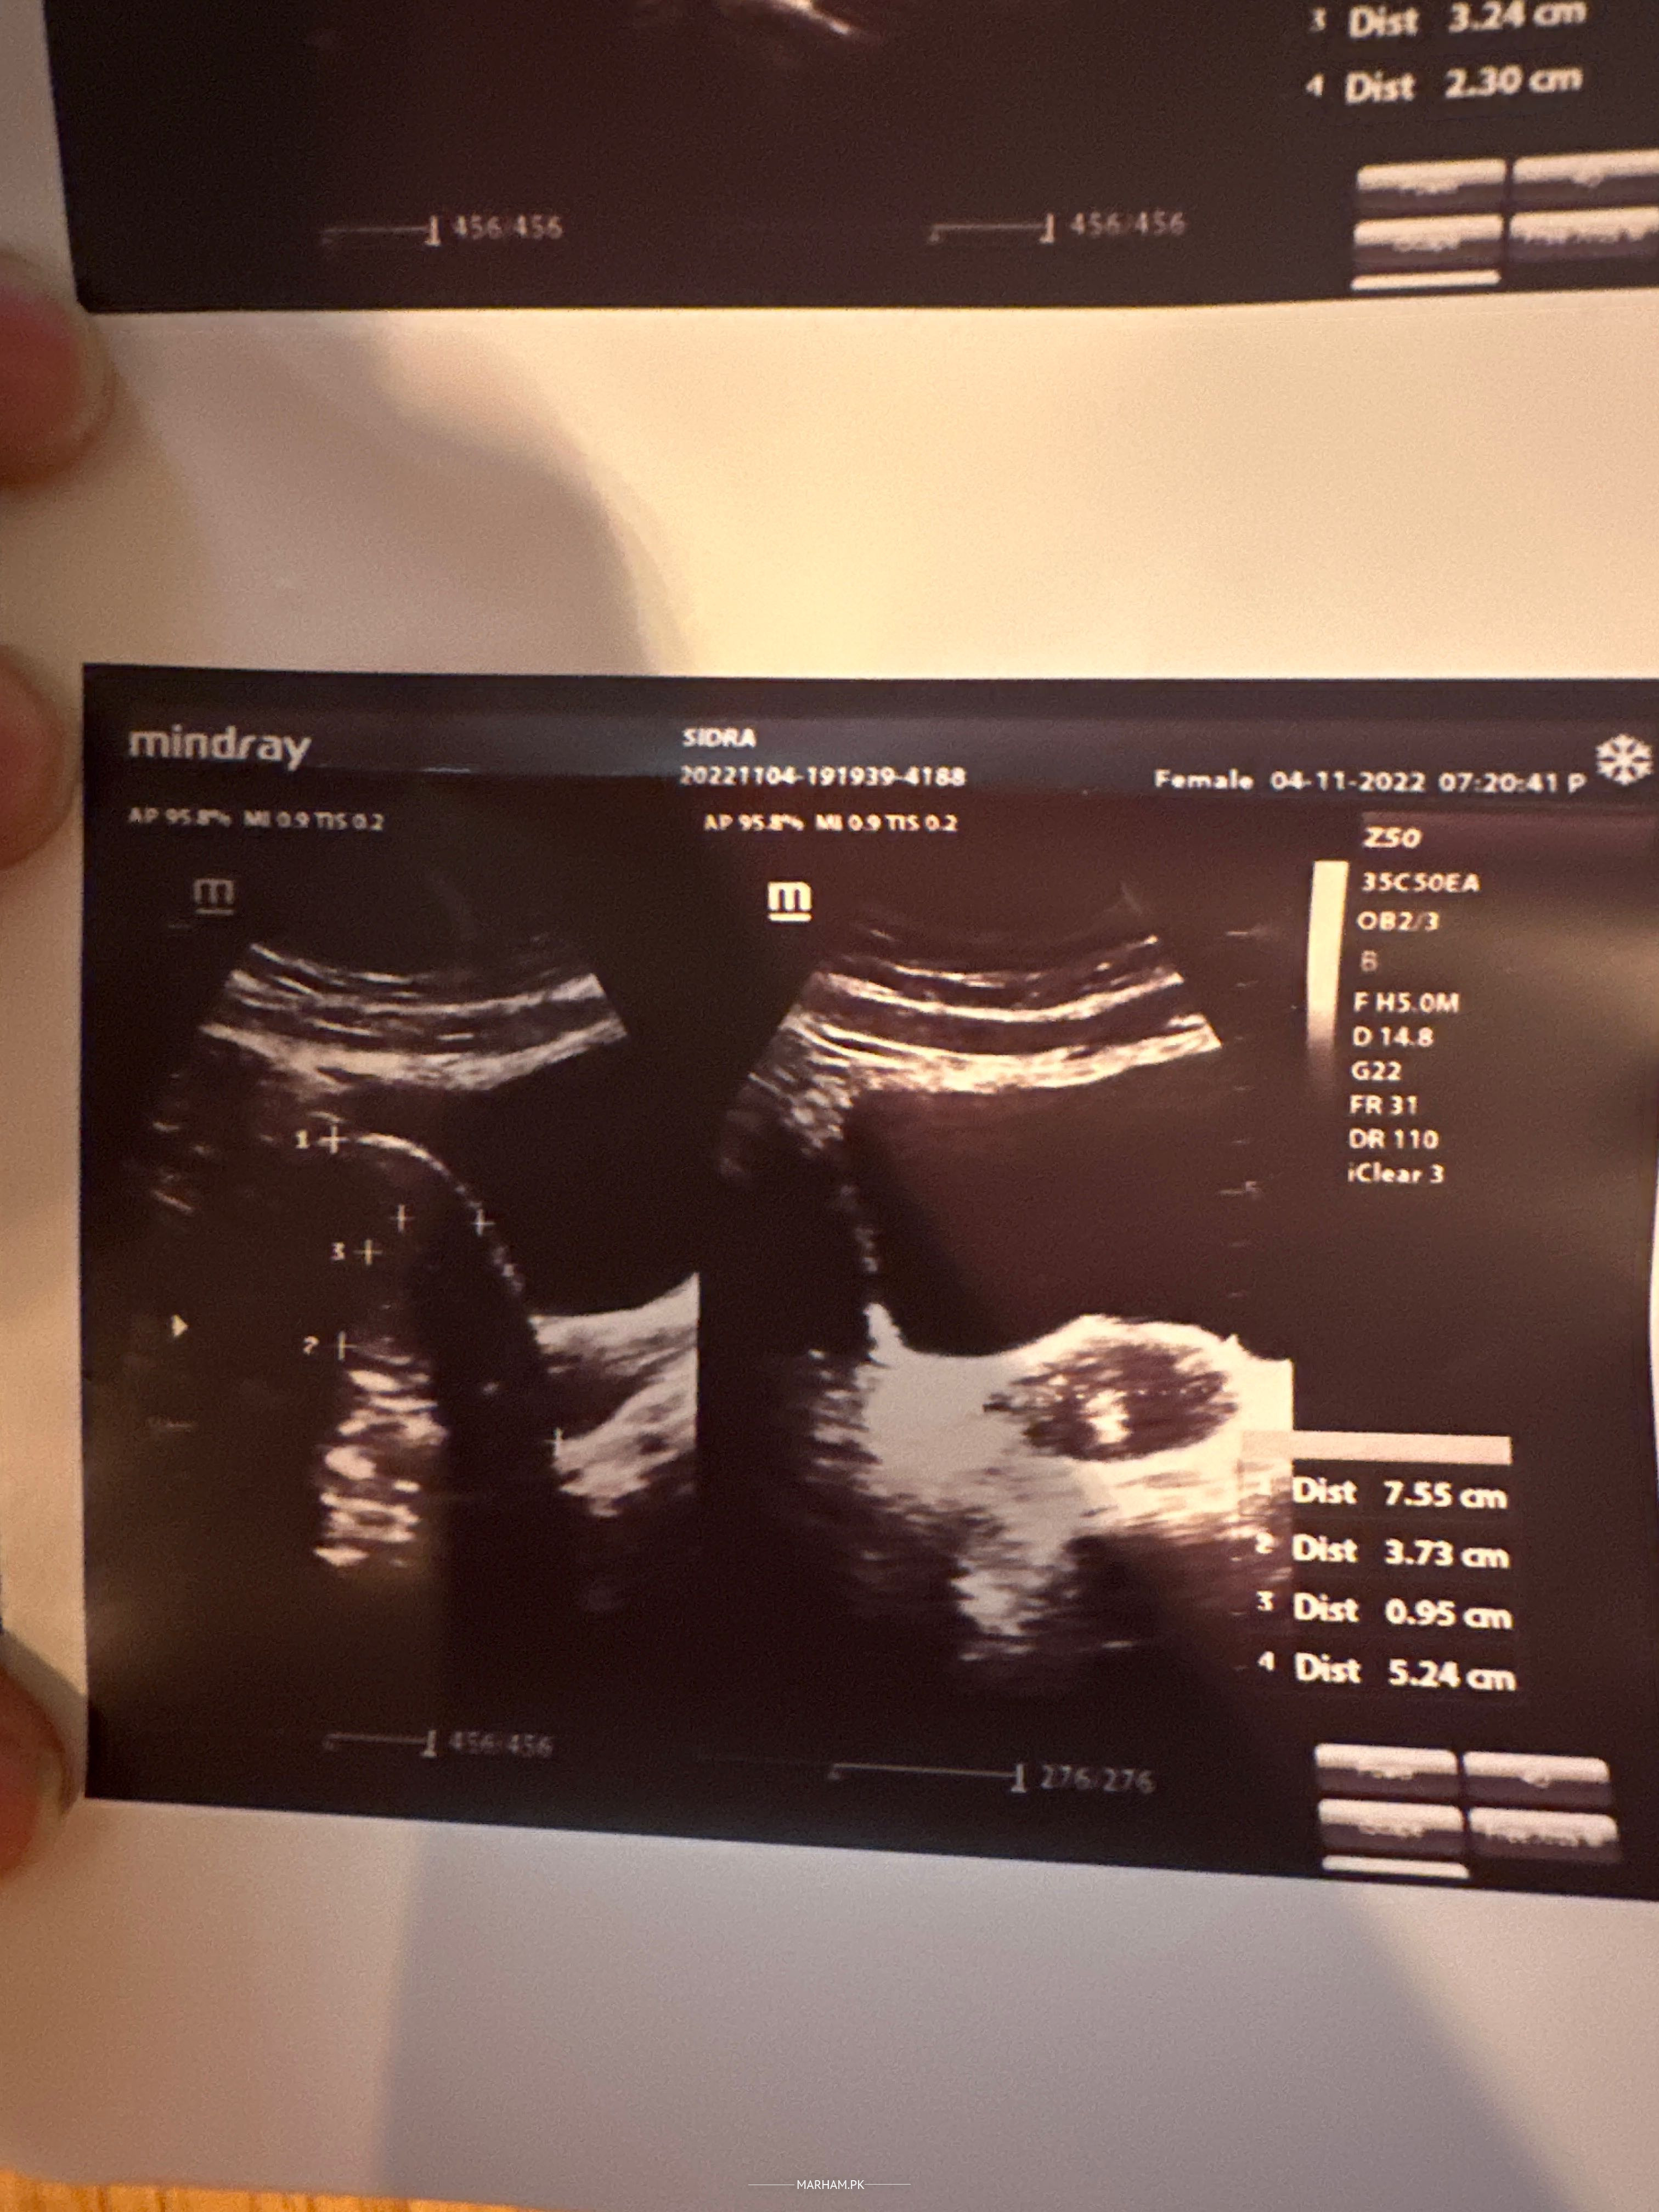

I have tiny follicles in ovaries. I am attaching my reports. Please suggest me.

Your ultrasound shows a hormonal disorder and probably some infection.But why you had this ultrasound? Cycles disturbance? wt gain? trying to conceive? or any other reason. diagnosis and proper treatment need a detailed history.Both problems in ultrasound are totally manageable.For consultation contact.

they mentioned that u have PCO.any wt gain hx .acne or excessive hair growth? what about period?what is ur complain?why u did ultrasound .then can give treatment

It’s pcod advice Hormonal assay

PCOS can not be diagnosed on just ultrasound findings.My dear it depends what u r looking for..either pregnancy or regular periods.My dear visit me at MEDICSI Islamabad if u r interested.